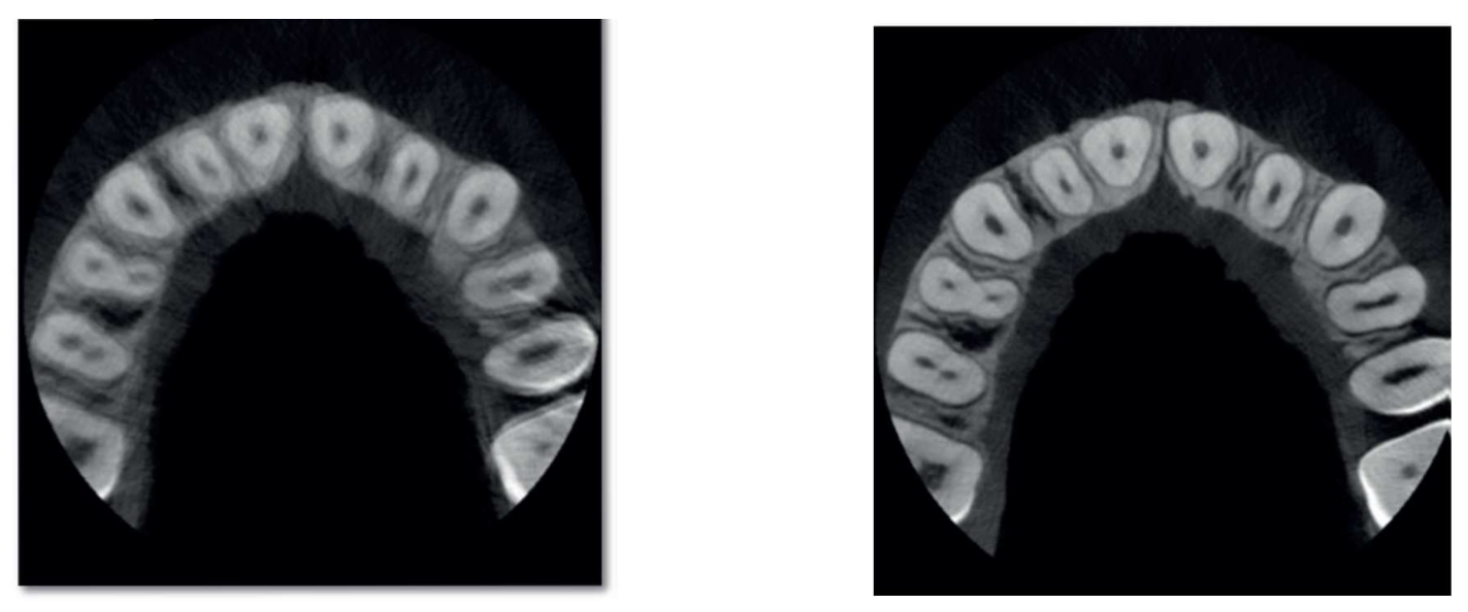

A CBCT (Cone Beam Computed Tomography) scan is a 3D dental imaging technology that captures detailed views of teeth, jawbone, nerves, and surrounding structures using a rotating cone-shaped X-ray beam.

CBCT = 3D dental imaging

X-ray = 2D flat image

This difference is not just visual, it directly impacts diagnostic accuracy and treatment outcomes.

The fundamental difference between CBCT and conventional X-rays lies in depth. CBCT provides a true 3D understanding of anatomy, while X-rays offer a flat 2D projection making them suitable for different clinical purposes.

| Image Type | 3D volumetric | 2D flat |

| Detail Level | High | Moderate |

| Depth Visibility | Yes | No |